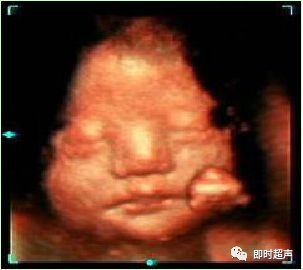

单脐动脉超声诊断

单脐动脉胎儿仅见一根脐动脉于膀胱一侧,经膀胱腹部横切面可判断左侧或右侧脐动脉缺如。羊水中脐带纵切面仅见两根血管并行或螺旋状排列, 横切时可见两个大小不一的圆环并行排列,彩色多普勒显示一红一蓝彩色血流信号。